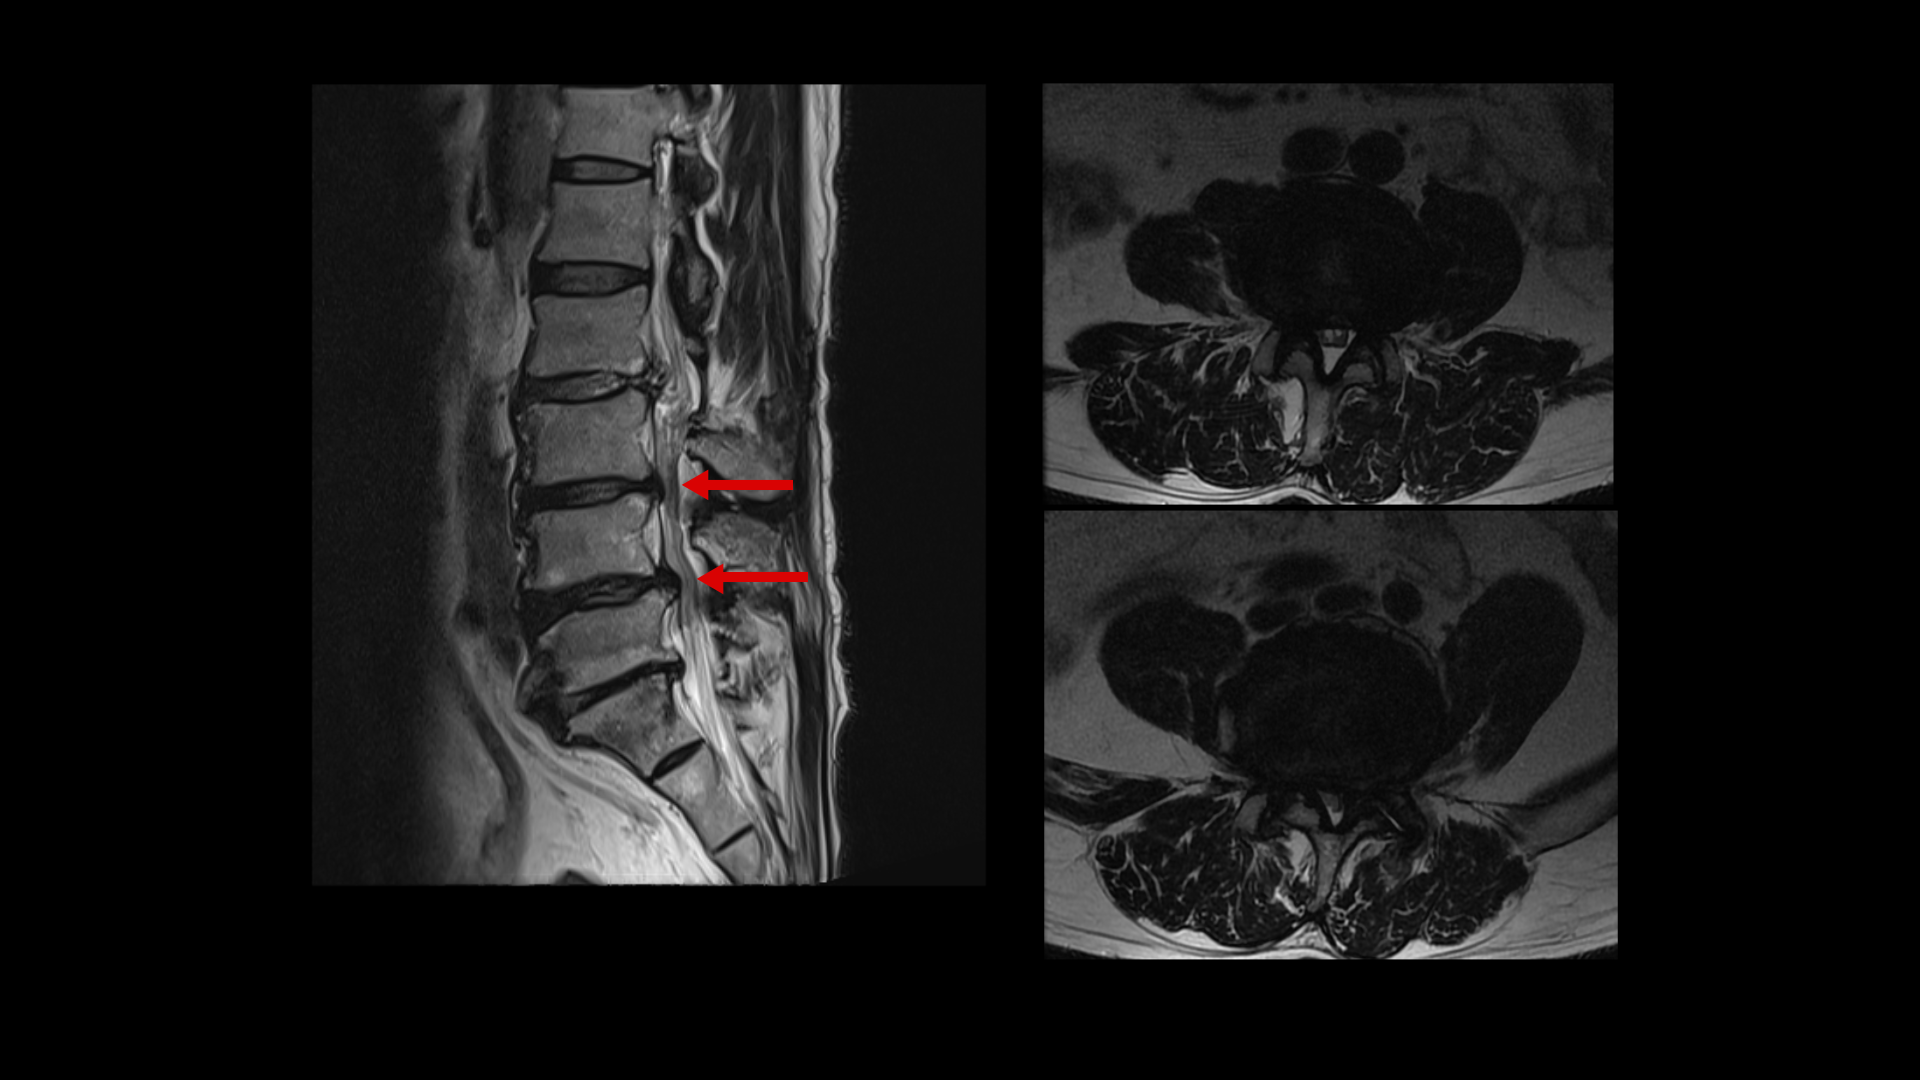

이분 MRI를 보면 네 마디에 퇴행성 디스크가 있고

두 마디에 중심성 협착이 있고

좌우로 나가는 신경구멍이 디스크와 협착으로 많이 좁아져 있습니다.

이분의 허리 MRI를 보면 2016년에 찍은 MRI와 2024년에 찍은 MRI가 있습니다.

이를 비교해보면 오른쪽, 왼쪽 다리의 마비 증상과 방사통의 원인인 걸로 추정되는 4번 5번과 5번 1번의 좌우 신경구멍이 비슷한 정도로 막혀 있습니다. 2016년과 2023년의 허리의 신경구멍이 좁아진 정도와 협착 정도는 비슷한 겁니다.